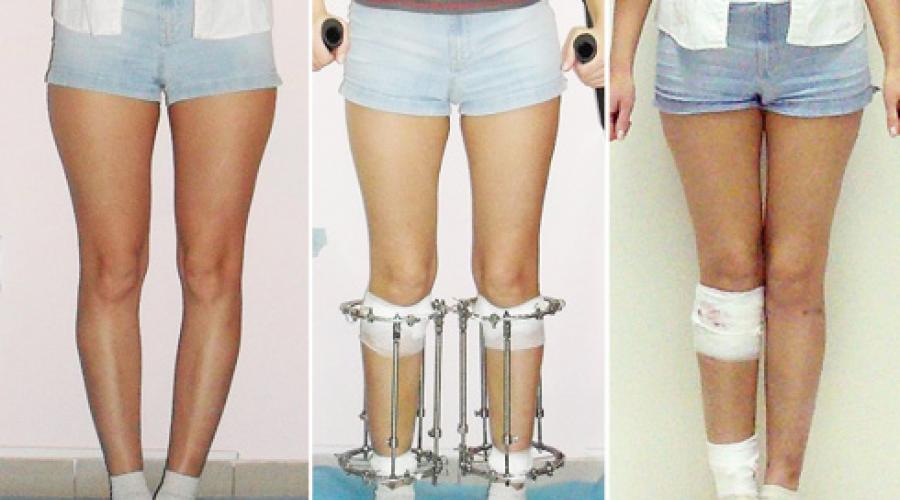

Аппарат Илизарова: принцип работы и применение

Раздел: Моменты озарения